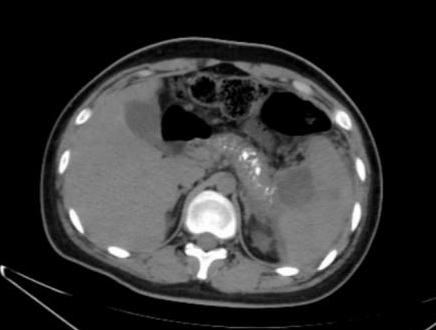

1 资料与方法患者男,17岁,主因“反复腹痛2年,加重伴发热2 d”来诊。患者于2019年起常于进食后出现腹部不适、纳差、腹痛,服用“胃药”对症处理后可好转,此后反复发作,频繁时半月发作一次。2020年9月下旬患者进食油腻食物后出现脐周及左中腹部胀痛,无恶心、呕吐,当地医院腹部CT提示:慢性胰腺炎急性发作,经对症治疗后2~3 d好转,此后每月有类似症状发作一次。2021年1月18日到本院基本外科门诊查胰腺功能,血清淀粉酶73 U/L,脂质624 U/L; 血钙正常; 血脂4项正常; 检查肿瘤指标,CA-125: 46.9 U/mL(升高),余为阴性; 甲状旁腺素正常; 血清IgG四项:IgG3 154 mg/L(降低),IgG4 1 600 mg/L(升高)。腹盆CT示胰腺多发钙化,胰尾囊肿形成(图 1)。1月22日患者进食汤面后出现腹部不适、纳差、乏力。1月24日晨起后出现腹部剧烈疼痛,伴发热,最高37.6℃,无恶心呕吐,无腹泻,于本院急诊就诊查血象正常,超敏C反应蛋白142.15 mg/L,胰腺功能:血清淀粉酶130 U/L, 脂质1 127 U/L。行腹盆CT检查示:胰腺饱满伴多发钙化,胰周脂肪密度稍增高,可见多发索条影,符合慢性胰腺炎改变(图 2)。予厄他培南抗感染及抑酸、补液等支持治疗后症状略好转,于1月26日收入本院急诊留观继续治疗。既往史:早产儿(32周),右桡骨小头骨纤维瘤术后,过敏性哮喘。个人史:否认饮酒史。家族史:父母体健,无其他特殊情况。

| 图 2 患者2021-01-24腹部CT |